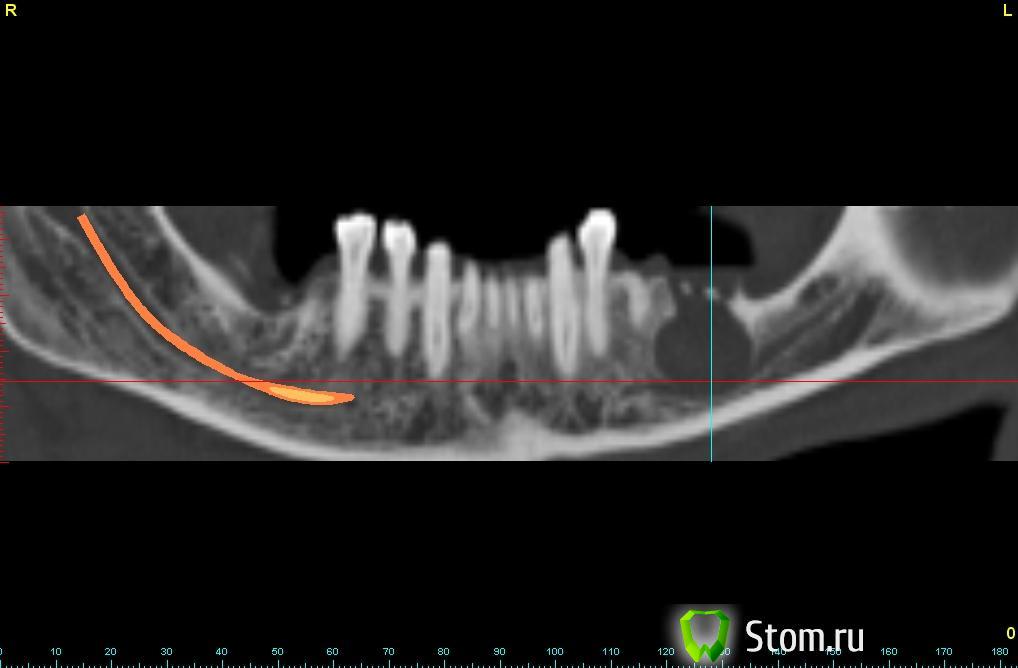

bullbull Опубликовано 13 декабря, 2011 Поделиться Опубликовано 13 декабря, 2011 Обратился пациент с желанием "привести рот в порядок". Зуб удален в городской стоматологии без рентген-обследования за 2 недели до снимка.Клинических проявлений со стороны кисты нет.Может ли оболочка кисты срастись с нервом?Ваши действия в этой ситуации? Ссылка на комментарий

Zborzh Опубликовано 13 декабря, 2011 Поделиться Опубликовано 13 декабря, 2011 Определенно , киста проросла в нижнечелюстной канал . Я бы просто через лунку удаленного зуба убрал на сколько можно оболочку кисты , а затем вел бы рыхлой йодлформной турундой , промывал бы через день хлоргексидином. Ссылка на комментарий

kriokov Опубликовано 13 декабря, 2011 Поделиться Опубликовано 13 декабря, 2011 Может ли оболочка кисты срастись с нервом?нет Ссылка на комментарий

kriokov Опубликовано 14 декабря, 2011 Поделиться Опубликовано 14 декабря, 2011 А как же возможность спонтанного перелома нижней челюсти? Может стоит зашинировать? Чем заполнить полость в кости?СПОНТАННО здесь нечему ломаться, кортикальная толстая с трех сторон от дефекта. Восполнять дефект можно сразу, если всю оболочку удалим- цистэктомия, а здесь больше на цистотомию тянет. Ссылка на комментарий